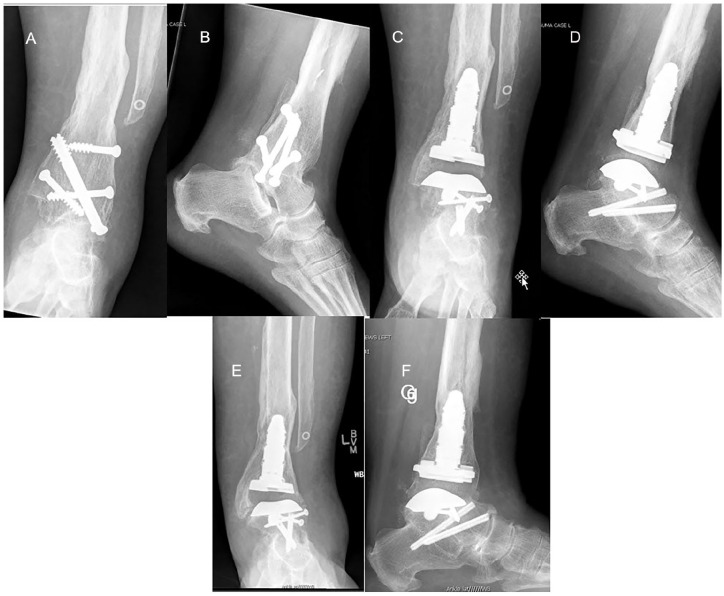

Methods: Between May 2010 and August 2019, 27 patients underwent conversion using a prosthesis with an intramedullary tibial component, 21 of which were available for the study. Six patients had a deficient distal fibula, and 5 were available for follow-up. Our primary outcome measure was having a total ankle arthroplasty in place. Secondary outcomes were evaluated postoperatively with a visual analog scale, the American Orthopaedic Foot & Ankle Society (AOFAS) ankle and hindfoot score, a satisfaction survey, and radiographic assessment of the arthroplasty and any concomitant hindfoot fusions.

Results: Mean follow-up for all patients was 7.6 (2.6-11.8) years, with follow-up of the deficient fibula group of 8.2 (4.9-11.8) years. Complications included malleolar fracture with or without subsequent surgery (n = 5), varus deformity (n = 1), and wound dehiscence or infection (n = 2). At final follow-up, all patients, including the 5 with a deficient distal fibula, had an intact ankle arthroplasty, although 3 with intact fibulas had undergone prosthetic revision. Postoperative dorsiflexion was 4.5 ± 5.1 degrees and plantarflexion 20.9 ± 13.37 degrees. There were no pseudarthroses in the 11 patients with concomitant hindfoot arthrodesis. Mean (±SD) VAS score was 4.4 ± 3.0 and AOFAS score was 71.2 ± 21.7. Sixty-seven percent reported that they were satisfied or very satisfied, with 16% dissatisfied or very dissatisfied. One of the deficient fibula patients was very dissatisfied. Seventy-six percent had no limitations with activities of daily living and two-thirds of those had no limitations at all.